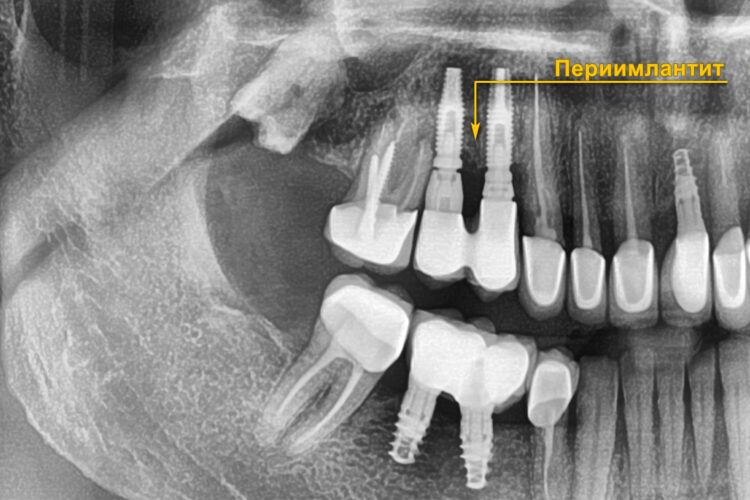

Основное осложнение, которое мы встречаем — это переимплантит (воспаление тканей вокруг имплантата).

Переимплантит может появиться по многим причинам, например:

- перегрев кости. Когда имплант устанавливается без физиодиспенсера (нет охлаждения сверла и, как результат, перегревается кость)

- недостаточная гигиена полости рта

- перегрузка импланта. Происходит из-за неправильного расположения имплантата в кости.